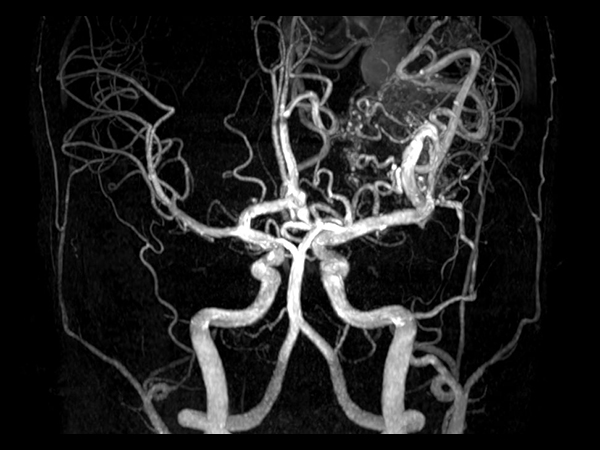

Pediatric brain with AVM

Pediatric patient with frontal brain AVM. MultiVane XD is used to achieve high resolution diagnostic images, even in the case of severe patient motion. SWIp sequence is added to acquire exquisite susceptibility contrast. The 3D sequences with isotropic voxel size enable reformats in any plane without loss of resolution. And 4D-TRAK XD, a fast, dynamic contrast-enhanced MR Angiography method allows to achieve high spatial and temporal resolution simultaneously. Integration of Compressed SENSE acceleration technique enables speeding up of the entire exam.

Coronal 3D TOF MRACompressed SENSE